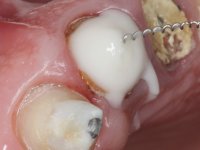

Endodontic treatments were performed and a metalic non screwed intra radicular post was placed on tooth 1.1. An alginate impression was made for laboratory confection of a reinforced acrylic provisional bridge, with teeth 1.1 and 2.2 as abutments and 2.2 as a pontic. After preparation of tooth 1.1 and root preparation of 2.1, the bridge was relined in mouth with self-polymerizable acrylic using a metal post for further retaining the prepared root canal on 2.1. Tooth 2.2 was cut at the gingival level to function as support. In the same session, the impression of the root canal of the 2.1 was made for the laboratory confection of a cast post and core. A double mixture technique with plastic tutor was used after previous canal vaseline with endodontic file and cotton. The provisional bridge was provisionally cemented and the cast post and core was made in the laboratory. Cast post and core cementation was made with resin-reinforced glass ionomer cement and the provisional bridge had to be readjusted to the new situation by removing the post at the site of 2.1. After careful surgical planning, a dental implant was placed, simultaneously with extraction of the root of tooth 2.2. The provisional bridge was placed by resting on the healing screw placed in the implant. The respected osteointegration period was 12 weeks, during which the provisional bridge was relined twice. After complete maturation of hard and soft tissues, definitive impressions were made. The gingival retraction technique was applied with an impregnated retraction cord and impression was performed using double mixture, open tray impression technique. A custom precious metal abutment implant was prepared in the lab, along with 3 metal caps to be used as infrastructures for the metal ceramic crowns. Particular care was taken in the confection of the cervical finishing line of the implant abutment, in order to follow the soft tissues emergence profile. Proof of infrastructures was done in the mouth being evaluated clinically and imagiologically. Collection of color information was done by the ceramist at the office. Ceramic was applied in the laboratory and the finished work was placed in the mouth after approval by the patient. Definitive cementation was made with resin-reinforced glass ionomer cement, and the first crown to be cemented was that of the implant, to facilitate removal of the excess.